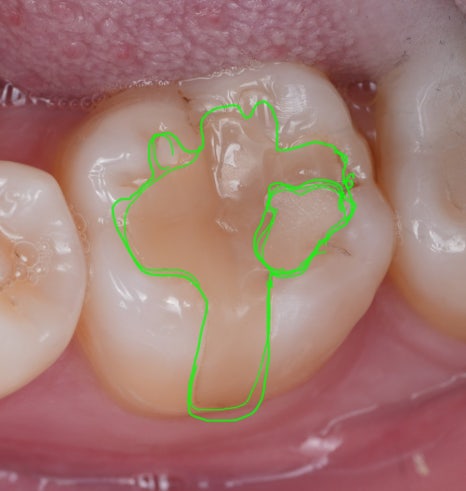

치아 가운데 하얗게 덧댄 것... 보이시죠?

심지어 레진으로 때운 곳도 온전치 않아 보이더라고요..^^;

큐레이를 통해 확인해 봐도 인레이치료 한 경계를 따라 붉은빛으로 문제가 있다는 것을 보여주네요.

큐레이는 특정 파장의 푸른 가시광선을 치아에 비추면 세균이 많은 부위에 붉은 형광빛을 띠어요.

먼저, 인레이를 제거했습니다.

겉으로는 멀쩡해 보이죠? 큐레이로 한 번 확인해 볼게요.